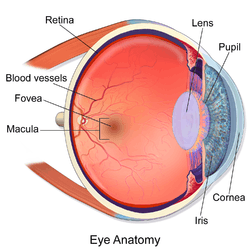

Human eye cross-sectional view, with macula near center. | |

The macula or macula lutea (from Latin macula, "spot" + lutea, "yellow") is an oval-shaped pigmented area near the center of the retina of the human eye. It has a diameter of around 5.5 mm (0.22 in). The macula is subdivided into the umbo, foveola, foveal avascular zone (FAZ), fovea, parafovea, and perifovea areas.[1] After death or enucleation (removal of the eye) the macula appears yellow, a color that is not visible in the living eye except when viewed with light from which red has been filtered.[2] The anatomical macula at 5.5 mm (0.22 in) is much larger than the clinical macula which, at 1.5 mm (0.059 in), corresponds to the anatomical fovea.[3][4][5] The clinical macula is seen when viewed from the pupil, as in ophthalmoscopy or retinal photography. The anatomical macula is defined histologically in terms of having two or more layers of ganglion cells.[6] The umbo is the center of the foveola which in turn is located at the centre of the fovea.